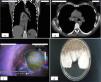

Mujer de 52 años, con antecedentes de 3 neumonías y asma. Consultó por disnea, tos crónica y febrícula. La analítica mostró eosinofilia del 7,7% (0,5×109/l) e inmunoglobulina E total (Ig ET): 6.680UI/l. El prick test y la prueba de radioalergoabsorbencia (RAST) fueron positivas para Aspergillus. La tomografía computarizada se muestra en las figuras 1a y b. En la broncoscopia (fig. 1c) un gran tapón mucoso, purulento y espeso ocupaba la entrada del árbol derecho. En el broncoaspirado se observaron micelios fúngicos y creció abundante Aspergillus terreus (fig. 1d). La citología mostró células inflamatorias y estructuras micóticas compatibles con hifas.

a y b) Imagen de tomografía computarizada coronal y axial, donde observamos en la grabación de mediastino un material de alta densidad (correspondiente al tapón mucoso) que ocupa casi todo el árbol bronquial derecho, parcialmente desde su entrada en el bronquio principal, bronquio intermediario en su totalidad, hasta llegar ocluyendo el bronquio del lóbulo inferior y medio (flechas negras). Provocando atelectasia parcial del parénquima dependiente de estos bronquios lobares (flecha blanca). También se objetivaron bronquiectasias varicoides bilaterales en la grabación de parénquima; c) Imagen broncoscópica del tapón mucoso protruyendo desde el bronquio fuente derecho justo antes de ser aspirado; d) Colonias de Aspergillus terreus aisladas en agar Sabouraud-cloranfenicol, con su característico aspecto blancas y algodonosas que se tornan pulverulentas o granulares de color canela-café.